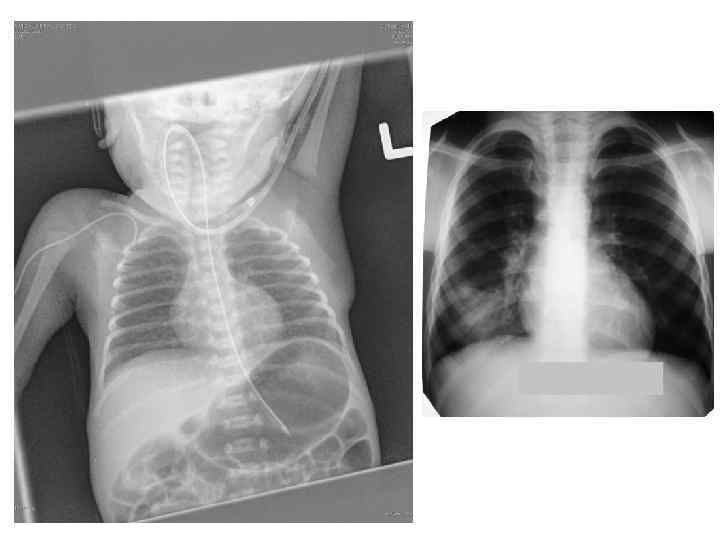

• Грудная клетка имеет форму усеченного конуса. Большой диаметр нижней грудной клетки обусловлен высоким расположением органов брюшной полости, особенно печени. После первого вдоха легкие расправляются, верхняя часть грудной клетки несколько расширяется, верхние ребра принимают почти горизонтальное положение. • The thorax has the shape of a truncated cone. The large diameter of the lower rib cage due to the high location of the abdominal organs, especially the liver. After the first breath the lungs are straightened, the upper part of the chest somewhat expands the upper ribs take a nearly horizontal position.

Дыхательная система Respiratory system • Нос короткий, нижний носовой ход недоразвит, а остальные — узкие. Слизистая оболочка полости носа тонкая, обильно снабжена кровеносными сосудами, склонна к отеку. • Легкие новорожденного богаты кровеносными сосудами, межуточной тканью и бедны эластической тканью. Лимфатические щели и капилляры широкие. Вследствие этих особенностей легкие более полнокровны, менее воздушны и эластичны, что создает условия для возникновения застойных явлений и развития инфекции. • The nose is short, the lower nasal passage underdeveloped, and the rest narrow. The mucous membrane of the nasal cavity is thin, richly supplied with blood vessels, prone to edema. • Lungs of a newborn is rich in blood vessels, interstitial tissue and is poor in elastic tissue. Lymphatic capillaries and cracks wide. Due to these features light a fuller, less airy and stretchy, which creates conditions for the emergence of stagnation and the development of infection.

• У новорожденных дыхание частое и поверхностной, характерны аритмия и лабильность дыхания. Число дыхательных движений у доношенного новорожденного от 40 до 50— 60 в 1 мин. • Становление функции дыхания у новорожденных происходит при участии легочного сурфактанта (антиателектатического фактора). При недостатке сурфактанта (например, при гипоксии) развивается синдром дыхательных расстройств (СДР). • Newborns breathing is frequent and superficial, characterized by lability and arrhythmias breathing. The number of respiratory movements in full-term newborn from 40 to 50 -60 in 1 min. • The formation of the respiratory function in newborns occurs when the pulmonary surfactant (antiateroskleroticescoe factor). With a lack of surfactant (e. g. , during hypoxia) develops respiratory distress syndrome (SDR).